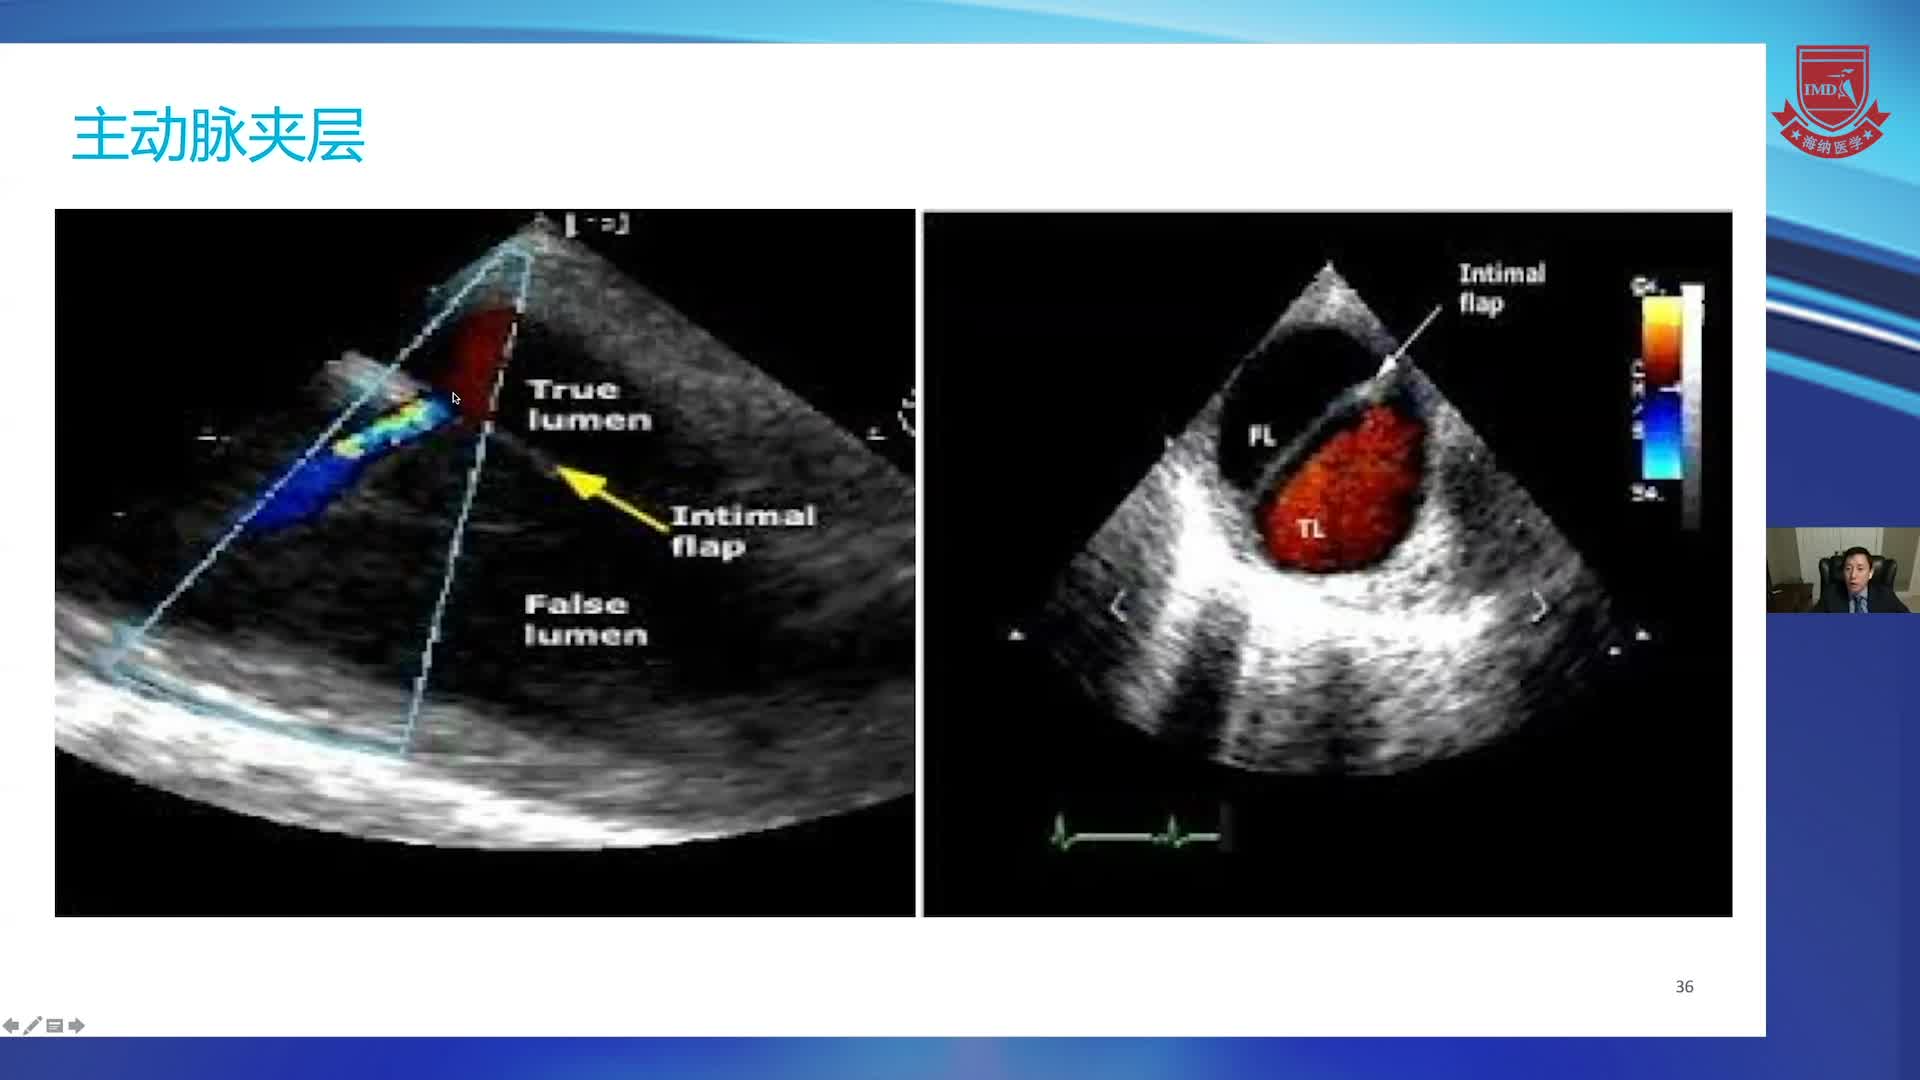

从“结构显像”到“容积定量”34D TEE在心脏手术中的应用--朱斌(1)